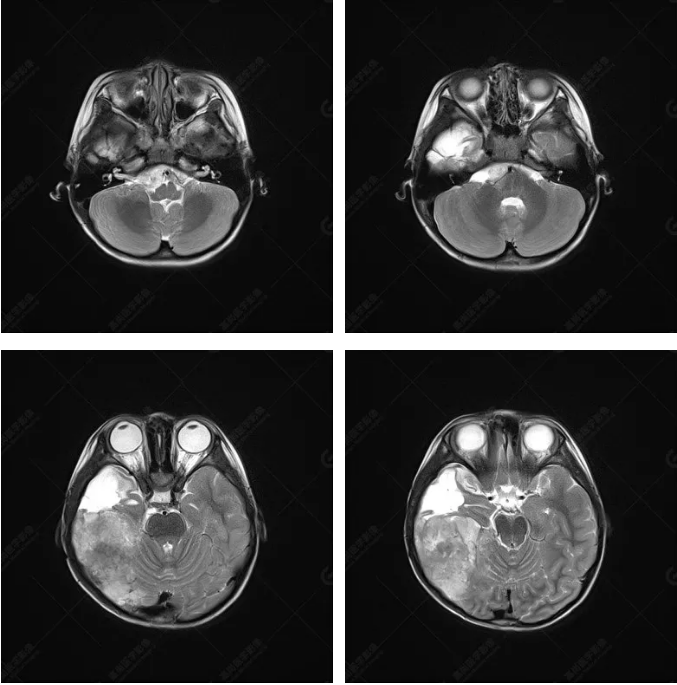

右側(cè)顳葉腫瘤切除術(shù)后(具體不詳):右側(cè)顳部骨質(zhì)不連續(xù)呈術(shù)后改變,右側(cè)顳葉術(shù)區(qū)見(jiàn)片狀長(zhǎng)T1長(zhǎng)T2信號(hào)影,F(xiàn)LAIR呈低信號(hào);術(shù)區(qū)后方右側(cè)顳枕葉見(jiàn)一巨大占位性病變影,邊界欠清,大小約6.2×5.8×4.3cm(前后×左右×上下),信號(hào)不均勻,T1WI呈等稍低信號(hào)間雜少許高信號(hào),T2WI呈高稍低混雜信號(hào),DWI示部分病灶彌散受限,相應(yīng)ADC圖減低,磁敏感序列見(jiàn)部分呈極低信號(hào),增強(qiáng)掃描可見(jiàn)明顯不均勻強(qiáng)化,鄰近硬腦膜及小腦幕增厚并明顯強(qiáng)化;另延髓右前方及右側(cè)橋小腦角區(qū)見(jiàn)一不規(guī)則形異常信號(hào)影,大小約3.2×1.3×3.7cm(左右×前后×上下),呈長(zhǎng)T1稍長(zhǎng)T2信號(hào),F(xiàn)LAIR呈等信號(hào),DWI未見(jiàn)受限,增強(qiáng)后明顯均勻強(qiáng)化,鄰近腦膜明顯強(qiáng)化。鄰近腦實(shí)質(zhì)及右側(cè)顳角明顯受壓;左側(cè)大腦半球未見(jiàn)局灶性信號(hào)異常,中線結(jié)構(gòu)稍左移。

右側(cè)顳葉腫瘤切除術(shù)后:現(xiàn)術(shù)區(qū)后方右側(cè)顳枕葉及延髓右前方占位,右側(cè)顳枕部硬腦膜及小腦幕明顯強(qiáng)化,結(jié)合既往影像資料,考慮為胚胎源性惡性腫瘤,如非典型畸胎樣/橫紋肌樣瘤(AT/RT)或原始神經(jīng)外胚層腫瘤(PNET)。